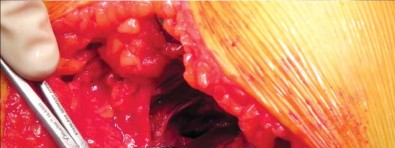

إدارة الأنسجة الرخوة وخلع رأس الفخذ

تُشق اللفافة العريضة والألياف الأمامية للعضلة الألوية الكبرى التي تتصل باللفافة العريضة قريبًا باستخدام الكي الكهربائي بما يتماشى مع شق الجلد. يتم إزاحة الجراب المدوري خلفيًا للمساعدة في رؤية العضلة الألوية الوسطى والعضلة المتسعة الجانبية. يتم رفع الجزء الأمامي من العضلة الألوية الوسطى عن المدور الكبير باستخدام الكي الكهربائي، ثم يتم تشريحه بشكل غير حاد بما يتماشى مع أليافه بزاوية 45 درجة أمامية-قريبة عند تقاطع الثلثين الأوسط والأمامي للعضلة. يقتصر التشريح على أقل من 3-4 سم باتجاه الرأس من طرف المدور الكبير لتجنب إصابة العصب الألوي العلوي. في غلاف مستمر مع العضلة الألوية الوسطى، يتم رفع الجزء الأمامي من العضلة المتسعة الجانبية عن حافة العضلة المتسعة ويتم شقه بعيدًا بين ثلثيه الأوسط والأمامي. يتم وضع مبعد هومان غير حاد في شق العضلة الألوية الوسطى لسحب الألياف الخلفية وكشف طبقة من الدهون بين المستويات الألوية. تُشق الكبسولة خلف العضلة الألوية الصغرى وعلى طول الجانب العلوي من عنق الفخذ. يقوم المساعد بتباعد وثني وتدوير الطرف خارجيًا لخلع رأس الفخذ.